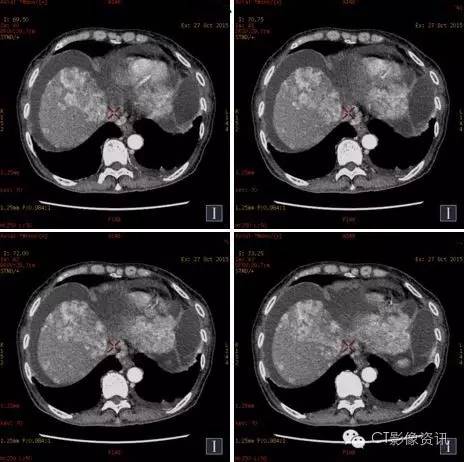

病例资料 女性,51岁,食欲下降5个月,上腹不适3个月。

70keV

碘(水)

CT诊断

小结 肝脏具有肝动脉和门静脉双重血供特点,肝硬化时由于门脉压力升高,导致门脉血供减少,为保证肝脏的营养肝动脉供血相对增加即肝动脉缓冲效应(Hepatic Arterial Buffer Response,HABR),以致肝脏的双重血供比例失调。 能谱CT可以实现物质分离功能,能够直接测量肝脏增强扫描各期肝实质的碘含量,并可计算出肝动脉碘分数(Arterial Iodine Fraction,AIF)与门静脉碘含量(PortalVenous Iodine Concentration,PVIC)。本例通过肝脏病变血供情况的定量分析,提供更多诊断信息。